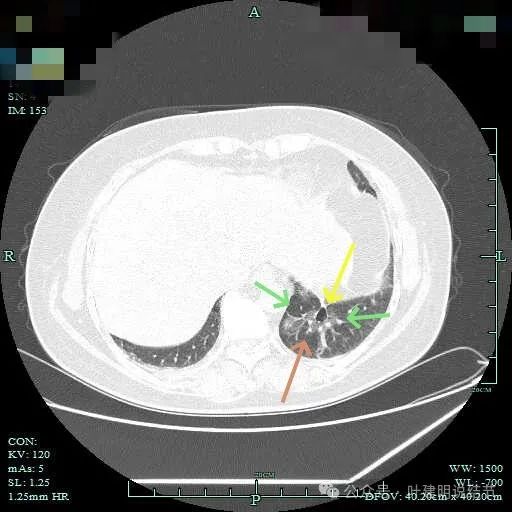

磨玻璃成分也很明显,考虑含贴壁亚型。

上图大部分是磨玻璃成分,边缘的毛刺征,表面有浅分叶。

上图层面已经基本上磨玻璃密度,轮廓清,灶内有囊腔样灶,表面不平。

边缘略显糊,与膈肌贴着。

远侧端有阻塞性炎症的表现,病灶在些层也是磨玻璃密度。

边缘区域略显轮廓不清。